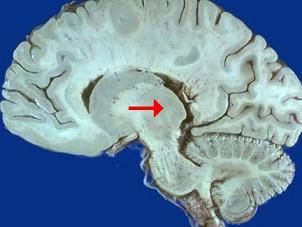

问题 如图箭头所示为大脑哪个部位 ( )

选项 A、松果体 B、中脑导水管 C、豆状核 D、尾状核 E、丘脑 一、单项选择题

答案 E